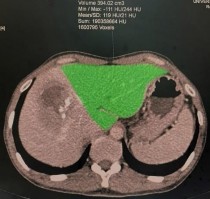

Thể tích gan bảo tồn là một chỉ số không thể thiếu trong phẫu thuật cắt gan lớn, đặc biệt là cắt gan phải và cắt gan thùy phải. Việc tính toán này được thực hiện dựa trên chụp X quang cắt lớp vi tính hoặc chụp cộng hưởng từ.

Hình 1.3. Thể tích gan trái bảo tồn đo bằng chụp X quang cắt lớp vi tính (Nguồn: Bệnh viện Đại học Y Dược TP.HCM)